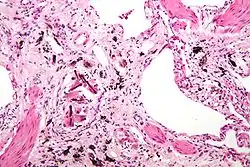

Micrograph of asbestosis (with ferruginous bodies), a type of pneumoconiosis. H&E stain. | |

- Asbestosis – asbestos: Develops from inhaling asbestos fibers, leading to lung tissue scarring and reduced lung function. Symptoms include shortness of breath, persistent cough, and chest tightness.[12] Historically prevalent among workers in shipbuilding, construction, and manufacturing, especially those handling insulation materials containing asbestos.[13]